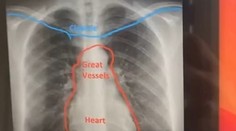

Röntgenová snímka odhalila, že dieťa prehltlo malý kríž.